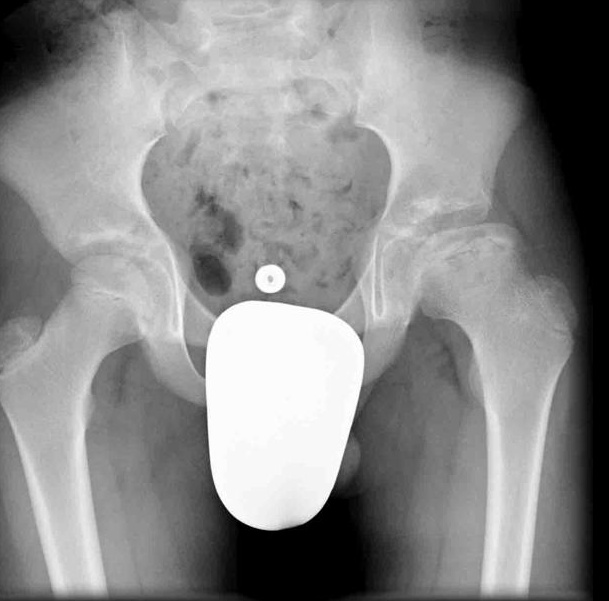

Diagnosis

X-ray imaging including AP and frog leg lateral of both hips shows the epiphysis remaining within the acetabulum while the neck displaces anteriorly and externally rotates leaving the head posterior to the neck. An early radiographic finding is epiphysiolysis where the growth plate is widened or shows increased lucency.,

Treatment

Treatment options are primarily surgical with percutaneous pinning of the slipped side. Treatment of this condition is emergent.,

Prophylactic pinning of the non-slipped side should be considered in cases of slipped capital femoral epiphysis related to hypothyroidism.

Complications of slipped capital femoral epiphysis include avascular necrosis, chondrolysis, and premature osteoarthritis.